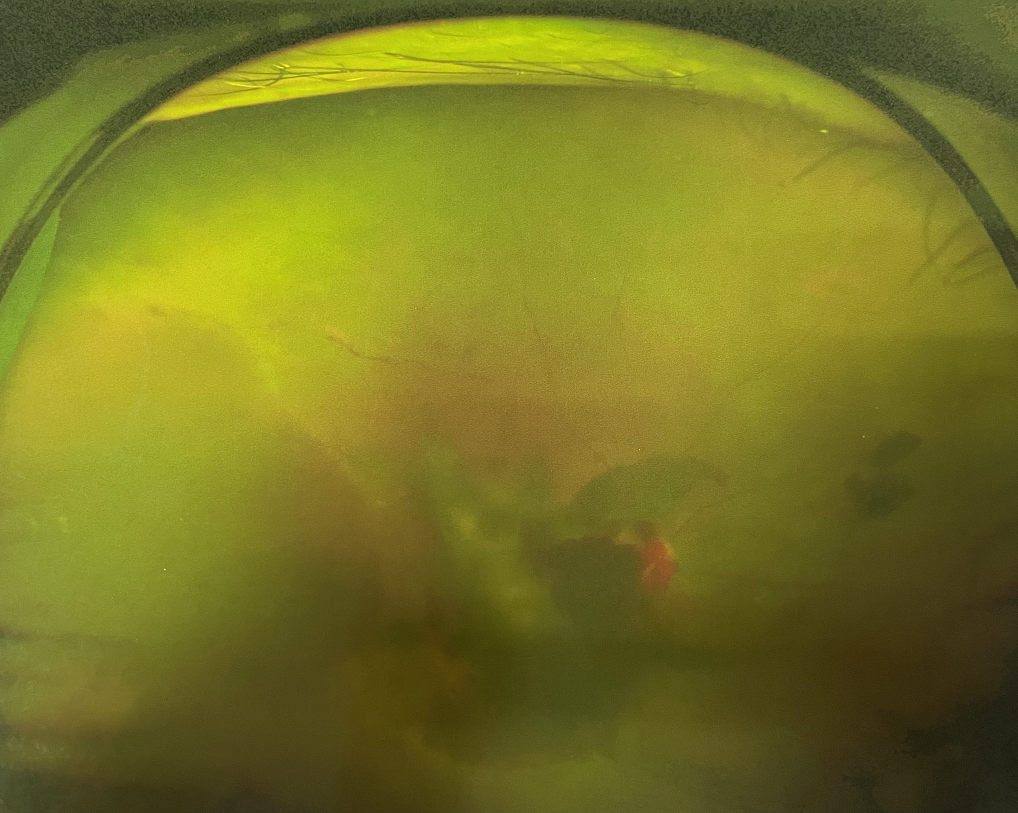

眼底出血

1、眼底出血

高血壓、糖尿病、動(dòng)脈粥樣硬化、高度近視、視網(wǎng)膜中央靜脈阻塞、脈絡(luò)膜新生血管性疾病等都可能造成眼底出血,引起中心視力下降、視物變形、黑影飄動(dòng)、飛蚊癥、閃光感等癥狀。